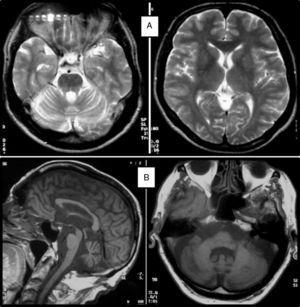

Cuadro clínicoUn cuadro de desequilibrio e inestabilidad, de inicio entre los 40 y 60 años de edad, suele ser el síntoma inicial de la SCA36. Este cuadro suele progresar lentamente y a él se le unirá ataxia apendicular con dismetría y disdiacocinesia, además de disartria de características cerebelosas o mixta (cerebelosa y bulbar)14-16,22,23. Raramente los enfermos llegan a precisar silla de ruedas antes de los 15 años de evolución. Alrededor del 80% de los pacientes presentan hipoacusia sensorial, afectación no mencionada en las primeras publicaciones de pacientes japoneses, aunque reconocida posteriormente15,24. En el 60-70% de los pacientes hemos detectado atrofia de la lengua con fasciculaciones, que puede contribuir a la mencionada disartria y, en pocos casos, a disfagia leve o moderada, ya que ningún paciente ha precisado la colocación de sonda nasogástrica o gastrostomía percutánea para asegurar su alimentación15,16,22–26. Nosotros no hemos encontrado otros síntomas o signos de enfermedad de motoneurona inferior fuera de la lengua, aunque sí se han notificado en algunos casos nipones. En más de la mitad de los casos está presente un cuadro piramidal con hiperreflexia y signo de Babinski con escasa o nula espasticidad. Otros signos clínicos posibles son nistagmo, sacadas lentas e hipométricas, ptosis palpebral y deterioro cognitivo ligero o moderado con un patrón de síndrome disejecutivo frontal25. En la figura 3 se detallan los porcentajes de los síntomas de comienzo y de las manifestaciones integrantes del cuadro clínico, correspondientes a nuestra serie inicial de 44 pacientes. No hemos encontrado clínica de disautonomía o alteraciones extrapiramidales, aunque Miyashiro et al.27 han comunicado recientemente un caso que asociaba parkinsonismo y distonía. Las aportaciones más relevantes de los medios complementarios en la SCA3615,16 se resumen en: A) En los estudios de resonancia magnética (RM) se observa atrofia cerebelosa desde el inicio de los síntomas; suele comenzar en el vermis superior y se extiende al resto del cerebelo para finalmente afectar al tronco cerebral y conformar un patrón de atrofia olivopontocerebelosa (fig. 4); no se detectan lesiones de sustancia blanca; en algunos casos puede ser evidente una moderada atrofia frontal. B) En los estudios neurofisiológicos se hallan valores normales para las velocidades de conducción motora y sensitiva; la denervación se restringe a la lengua en los pacientes gallegos. En el estudio de potenciales evocados somatosensoriales se encuentran retrasos de la conducción al estimular en miembros inferiores. El estudio de los potenciales evocados auditivos muestra ausencia o marcada reducción de amplitud de las ondas i y ii. En la audiometría es características una caída de 40 o más dB en frecuencias superiores a 2.500Hz. C) En los escasos estudios histopatológicos realizados se encontró pérdida de células de Purkinje, sobre todo en el núcleo dentado del cerebelo, y pérdida de neuronas motoras en el núcleo del hipogloso. No se observaron, tal como sucede en la ELA, inclusiones citoplasmáticas eosinofílicas tipo Bunina en motoneuronas del asta anterior medular.